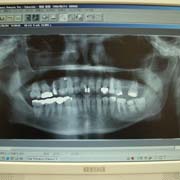

<デジタルレントゲン>

従来のレントゲンに比べ、被曝量が大幅に軽減されております。

又、鮮明な画像により、正確な診断が可能です。

現像までお待たせすることもなく、受診時間の短縮が可能です。

患者様にパソコンの画面上で直接ご確認頂けます。

(尚、上記レントゲン画像の掲載につきましては、患者様のご承諾済みです。)